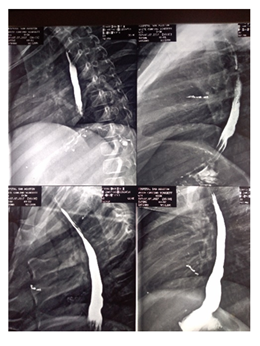

Figure3 A. Dilated stomach after passage of guide wire and first esophageal dilation. B. Normal gas distributiion on stomach and small bowel after 24hours.